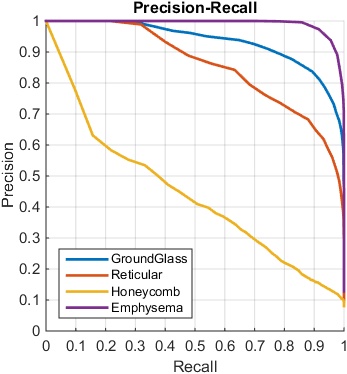

The classification results are shown using the ROC curves in Fig. 5, and F-scores are presented in Table 3 and Table 4 while setting the pathology presence thresholds to be and , respectively. The overall F-score is calculated based on the multi-label classification evaluation mentioned in Sec. 4.2. We obtain good results using the setting of but the quantitative results by setting are further improved, indicating that our algorithm may be robust to detect smaller ILD patterns and can tolerate some pixel-level annotation errors in LTRC. In our setting, pixel-level ILD annotations are not essentially required. Therefore the medical experts can simply provide the holistic CT slice-level labels on any lung CT image to indicate if there are ILD presences worth reporting, without annotating particular ILD image ROIs. It would considerably save the labeling time for experts to annotate the training dataset.

4.4 Results on Multi-label Regression CNN

We can treat the continuously-valued output vector, either in the form of pixel number counts or binary presence status, as the “classification confidence scores” after the multi-label regression CNN processes an input CT image. These regressed confidence scores can be compared against the ground truth binary ILD labels obtained by thresholding on as in Sec. 4.3. In this manner, ILD classification receiver operating characteristic (ROC) curves are generated. Our experiments are conducted via the three label converting functions or plots in Fig. 3. Two variations of CNN regression outputs to match the ILD occupied pixel numbers per-slice, or the binary ILD presence labels produce similar quantitative ILD classification results. The piecewise linear transformation (Fig. 3 Right) yields slightly inferior results.

Table 3 and Table 4 show the multi-label regression CNN results where the trained model regresses to the number of diseased pixels in each image. The use of a smooth cost function greatly improves the performance and constantly outperforms the cost function in all experiments by noticeably large margins. Fig. 6 illustrates some visual examples of successful or misclassified results. The first four examples are successfully detected cases, with multiple ILD patterns coexisting on the same slice. The last two are failure cases. Note that the first misclassified case is marked with two detected labels of “emphysema” and “ground glass”. Both emphysema and ground glass co-occur on this image but the pixel count of ground glass occupied spatial region does not meet the pathology threshold of . These qualitative results visually confirm the high performance demonstrated by our quantitative evaluation.

The overall performance of multi-label regression CNN when the smooth loss is employed is generally comparable with the multi-label classification CNN (Sec. 4.3). From Table 4 and 3, the smooth regression CNN performs slightly better overall and particularly for the ground glass class, but the multi-label classification CNN outperforms in the categories of reticular, honeycomb, and emphysema with moderate margins.